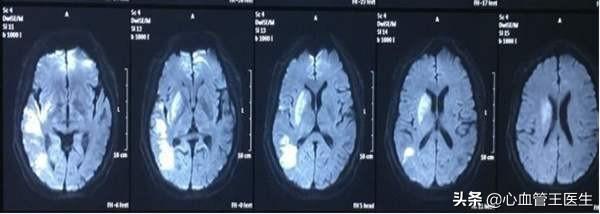

脳梗塞とは、脳の血管の一部が「閉塞」し、酸素やエネルギーを供給するための血液が流れなくなり、脳の組織や細胞が機能不全や壊死を起こす病気である。血管を塞いでいるものを「閉塞」という。血栓.脳梗塞は主に2つの方法で起こる。"地元"その主な理由は、ケースの大半を占めていた。脳動脈硬化脳梗塞の場合、破裂と出血によって血栓が形成され、血管の内腔を塞ぐ。別のタイプの血栓は「フィールド塞栓が脳血管の血流に乗って脳から遠ざかり、脳動脈を閉塞することで起こる脳梗塞の主な原因は、主に心臓由来のもので、心臓性脳梗塞とも呼ばれ、最も重要な原因は以下の通りである。心房細動。

要約すると、脳梗塞の主な原因は脳動脈硬化と心房細動である。。

長期的な高血圧がコントロールされていないか、コントロールが不十分な場合、血管の壁が肥厚し、内腔が狭くなり、アテローム性動脈硬化プラークが促進または悪化し、プラークのサイズが徐々に大きくなり、血管が狭くなったり、閉塞したりする。プラークは2種類に分けられ、1つは安定プラークと呼ばれ、この害は大きくありません。もう一つは、脆弱プラークとも呼ばれ、次のように呼ばれています。「犯罪者の盾「プラークの表面潰瘍、破裂、血栓形成、血栓による脳血管閉塞が脳梗塞を引き起こす。脆弱プラークは血管塞栓を引き起こす重要な因子であり、脳梗塞だけでなく心筋梗塞もその原因である。現在、心筋梗塞や脳梗塞を予防するためには、脆弱プラークを治療して安定プラークに変えることが非常に重要な対策となっている。

長期に高血圧をコントロールし続けると、左心房肥大が起こり、左心房肥大はやがて心房細動の発生につながり、心房細動の最大の危険は脳梗塞である。心房細動の血流の遅滞、心臓の血栓の形成、血栓が脳血管に走るために外れて、脳梗塞につながる。

長期高血圧によるラクナ脳梗塞の予後も比較的良好で、一般に死亡や障害などの後遺症に至ることはありませんが、ラクナ脳梗塞は急性発症することもあれば、緩徐に発症することもあり、一般に患者に眠気昏睡などの症状が現れることはありません、つまり、患者は脳梗塞の発生を意識して起きており、予後は良好ですが、再発しやすい病気ですので、予防をしっかり行うことが特に重要です。予防の鍵は、高血圧をコントロールし、さまざまな危険因子を予防し、対処することである。

脳血栓症の原因としては、動脈硬化が最も多く、次いで高血圧などが多い。 高齢者に発症し、発症前に高血圧、糖尿病、冠動脈疾患、高脂血症などの既往があることが多く、静かな状態や睡眠中に発症することが多く、中には発症前に一過性脳虚血発作を繰り返すことも多く、脳血栓症の患者は片側の脱力感、片麻痺、ろれつが回らない、失語などの症状がみられる。脳血栓症では、片側の手足の脱力、片麻痺、言語障害、失語症などがみられ、梗塞が大きい場合には、無気力、昏睡、脳ヘルニアなどで死に至ることもある。 治療は、急性期には脳保護療法、血栓溶解療法、回復期にはリハビリテーション療法、脳梗塞再発のハイリスク因子の予防などが中心である。